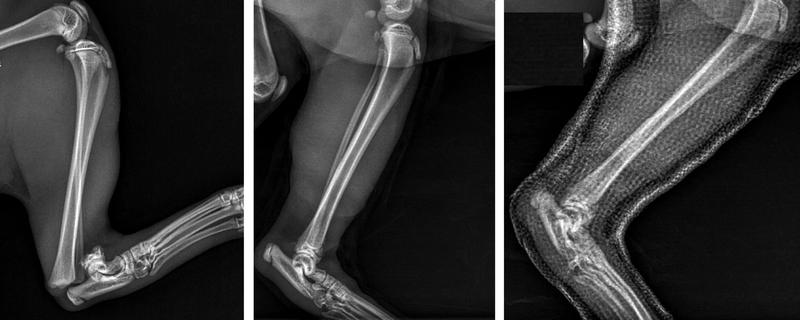

Kiedy dotrzesz do weterynarza, pomoc znajdzie się w zasięgu ręki. Specjalista z pewnością wykona zdjęcia rentgenowskie, aby dokładnie ocenić, co się wydarzyło. Leczenie można podzielić na dwa główne rodzaje: zachowawcze, na przykład poprzez założenie gipsu w przypadku prostego złamania, oraz operacyjne, co jest konieczne, gdy sytuacja jest bardziej skomplikowana. Bez względu na wybór metody, kluczowe staje się zapewnienie psu relaksu oraz minimalnego wysiłku fizycznego. Czasami warto rozważyć użycie klatki kenelowej, ale tylko wtedy, gdy Twój pupil zgodzi się na taki pomysł!